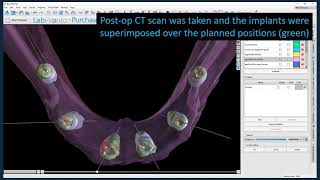

How to make a combination bone and tooth/tissue supported surgical guide video

How to make a combination bone and tooth/tissue supported surgical guide

How to make a combination bone and tooth/tissue supported surgical guide Bone Supported Surgical Guide

How to make a combination bone and tooth/tissue supported surgical guide

How to make a combination bone and tooth/tissue supported surgical guide Bone Supported Surgical Guide